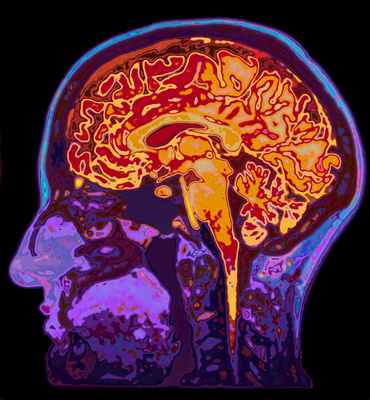

Так выглядит головной мозг человека.

Это сложнейшая структура, состоящая из множества различных образований, находящихся в тесном взаимодействии; осуществляющая проводящую, анализирующую, регулирующую и координирующую функции. Все движения тела, чувства человека, работа внутренних органов, его разум, интеллект, память, сознание, сон, бодрствование, всё контролируется головным мозгом. Мозг человека можно сравнить со сложнейшим компьютером с заложенными в него программами, постоянно модифицирующимися в течение жизни человека.

Схематически головной мозг можно разделить на доли: лобные, затылочные, височные, теменные; мозжечок, ствол мозга. Доли мозга покрыты корой, которая представляет собой совокупность высоко дифференцированных нейронов, осуществляющих высшую интегративную деятельность.